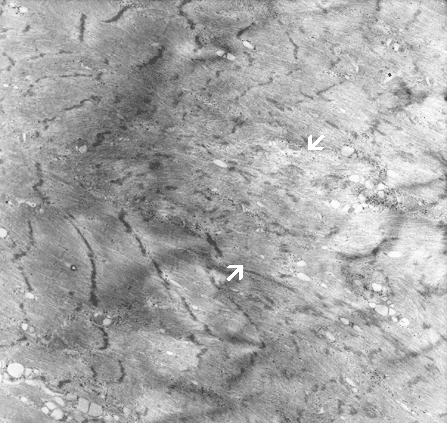

This is a higher magnification of the core in Panel I. Note that disturbance of architecture is extensive enough to cause total dissolution of Z-discs in some areas (in between àÝ). Reduction in the length of I-band is clearly demonstrated here. |